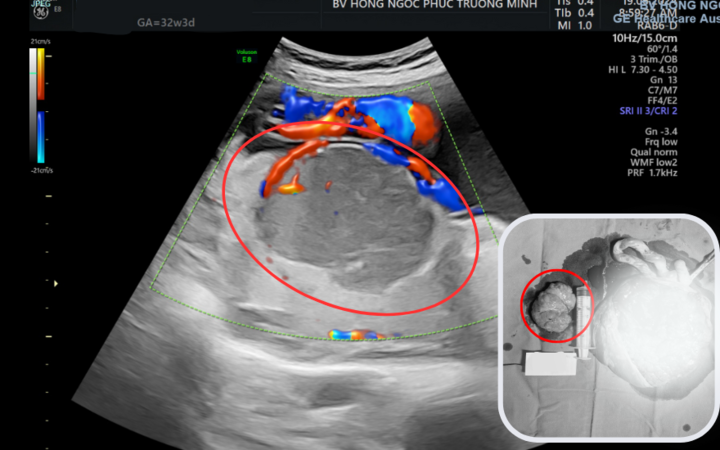

.png)

Động mạch khớp gối trước và sau khi nút động mạch